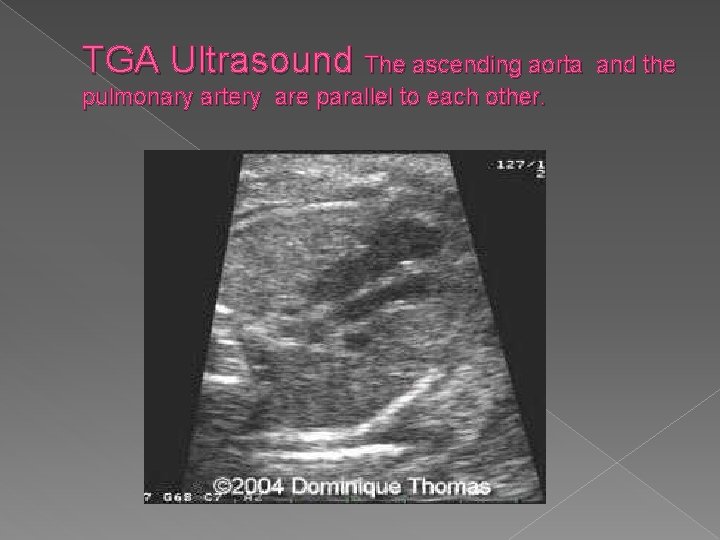

TGA Ultrasound The ascending aorta pulmonary artery are parallel to each other. and the